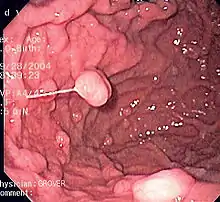

Clinical significance

Diseases

A series of radiographs can be used to examine the stomach for various disorders. This will often include the use of a barium swallow. Another method of examination of the stomach, is the use of an endoscope. A gastric emptying study is considered the gold standard to assess the gastric emptying rate.[46]

A large number of studies have indicated that most cases of peptic ulcers, and gastritis, in humans are caused by Helicobacter pylori infection, and an association has been seen with the development of stomach cancer.[47]